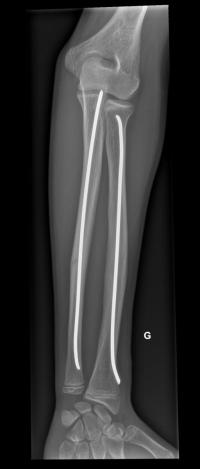

Fracture de l’avant-bras 31 mars 202519 mars 2024 par Damien Traitement Traitement orthopédique Embrochage centro-médullaire